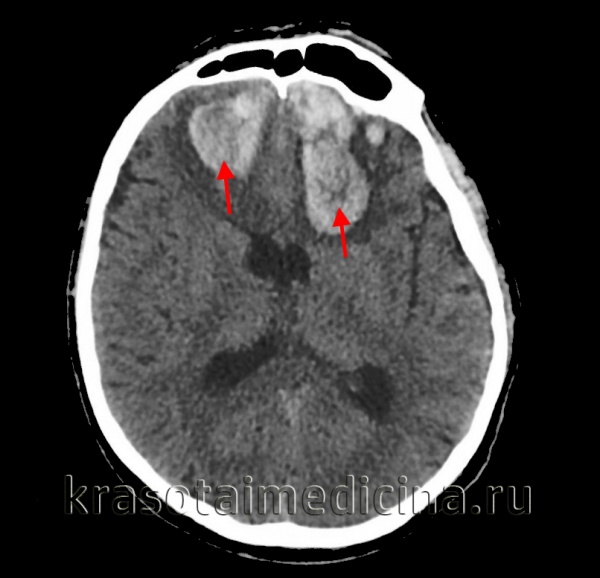

Медицинские аспекты и диагностика субдуральной гигромы мозга